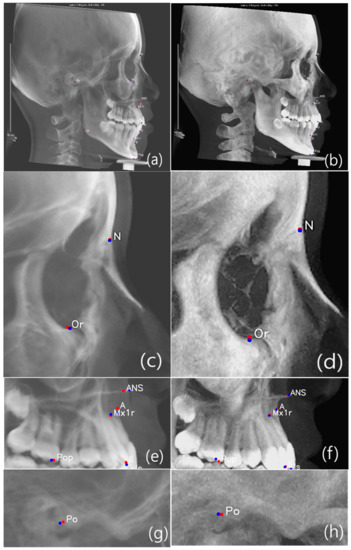

Figure 5.

Comparison of AI prediction between CBCT-LC (a,c,e,g,i) and MIP-LC (b,d,f,h,j); Orbitale c and d; Maxilla e and f; Porion g and h; and Mandible i and j. The red dot is manual identification (truth ground), and the blue dot is AI prediction.